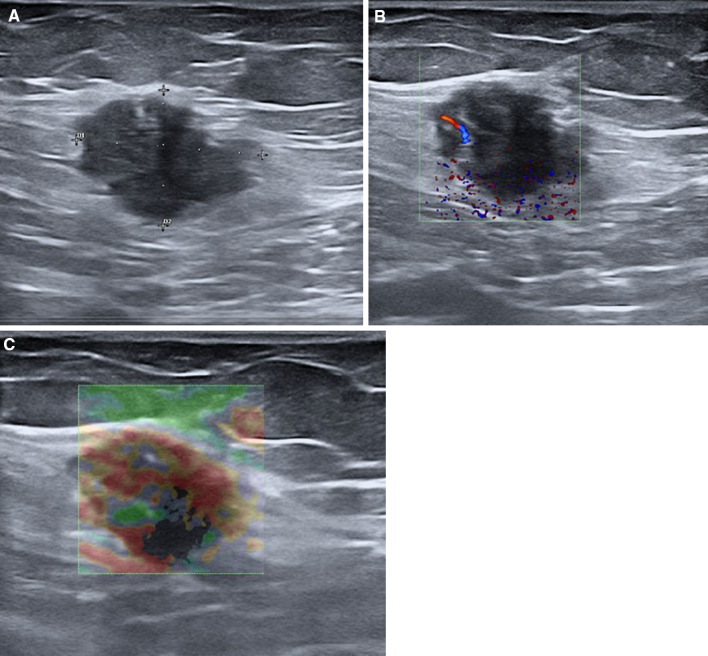

Fig. 12.

Endometriosis of subcutaneous tissues. B-mode ultrasound shows a hypoechoic mass inside the subcutaneous tissues (a) with intralesional vascular signals with color Doppler ultrasound (b) and a hard pattern with strain elastosonography (c)

Fig. 13.

Endometriosis of muscular tissues. B-mode ultrasound shows a hypoechoic mass inside the muscular tissues (a), with a hard pattern with strain elastosonography (b)

B-mode ultrasound images with a high-frequency linear probe can identify the presence of endometriosis foci inside the superficial tissues of the abdominal wall showing the hypoechoic nodule located inside the tissues (cutaneous, subcutaneous, or muscular) (Figs. 12a, 13a). Fine intralesional vascular spots are depicted with color-power Doppler (Fig. 12b), and a hard pattern of the mass is identified with the elastosonography strain modality (Figs. 12c, 13b) [76].